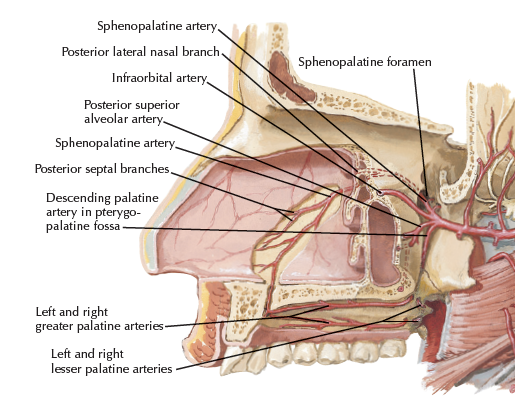

- Sphenopalatine a.

- 最終分支,進入 Sphenopalatine foramen,支配鼻竇

Artery

- Sphenopalatine a.

- Sphenopalatine a.

Paranasal sinuses